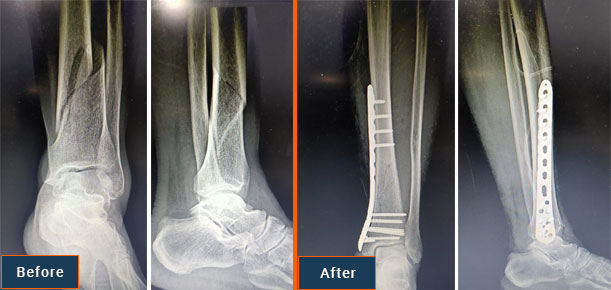

During a surgical procedure to set a fracture, the bone fragments are first repositioned (reduced) into their normal alignment. They are held together with special implants, such as plates, screws, nails and wires.

Internal fixation allows shorter hospital stays, enables patients to return to function earlier, and reduces the incidence of nonunion (improper healing) and malunion (healing in improper position) of broken bones.

Plates

Plates are like internal splints that hold the broken pieces of bone together. They are attached to the bone with screws. Plates may be left in place after healing is complete, or they may be removed (in select cases).